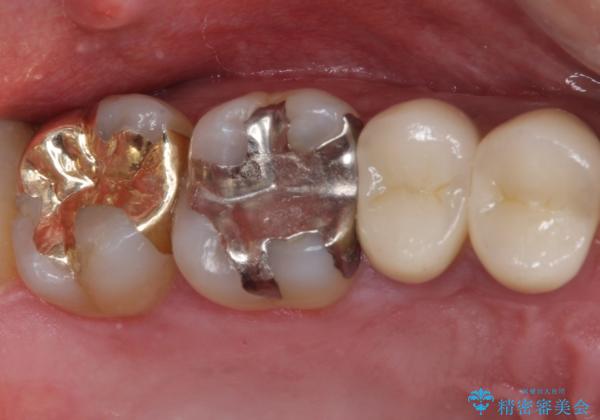

- 上の奥歯に装着されていた銀歯が外れてしまったとのことで来院された患者様です。

強い咬合力により銀歯と歯の間に隙間ができ、その隙間から虫歯となって外れてしまったと想像されました。

銀歯では歯と充填物の固さに違いがあり、再度外れてしまうリスクが高いため、固さが歯と近いゴールドインレー(PGAインレー)にて修復することとしました。